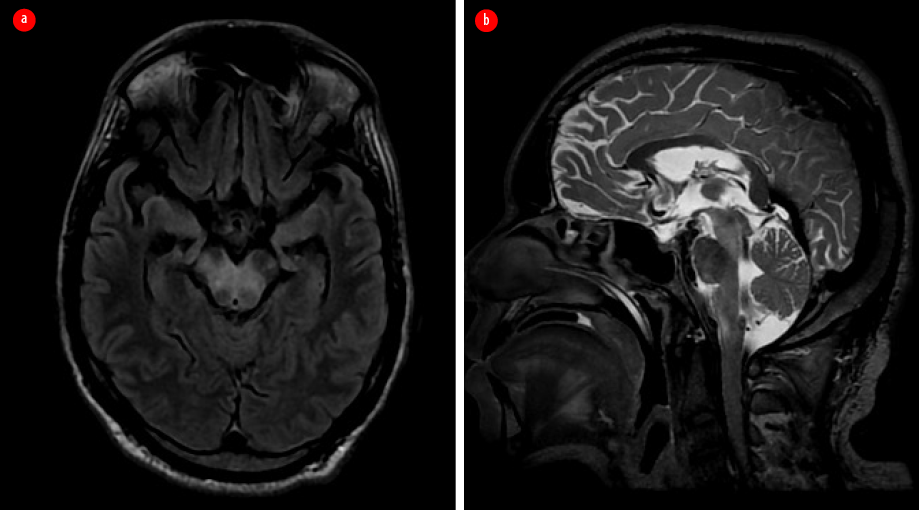

Ultrasonography of the abdomen revealed hepatosplenomegaly, prostatomegaly with abscess formation, and multiple splenic microabscesses [Figure 2]. The culture of his right knee aspirate yielded B. pseudomallei, but the blood culture was negative for the pathogen.

Figure 2: Ultrasonographic images of the abdomen. (a) Hepatosplenomegaly, prostatomegaly with abscess formation. (b) Multiple splenic microabscesses are seen.